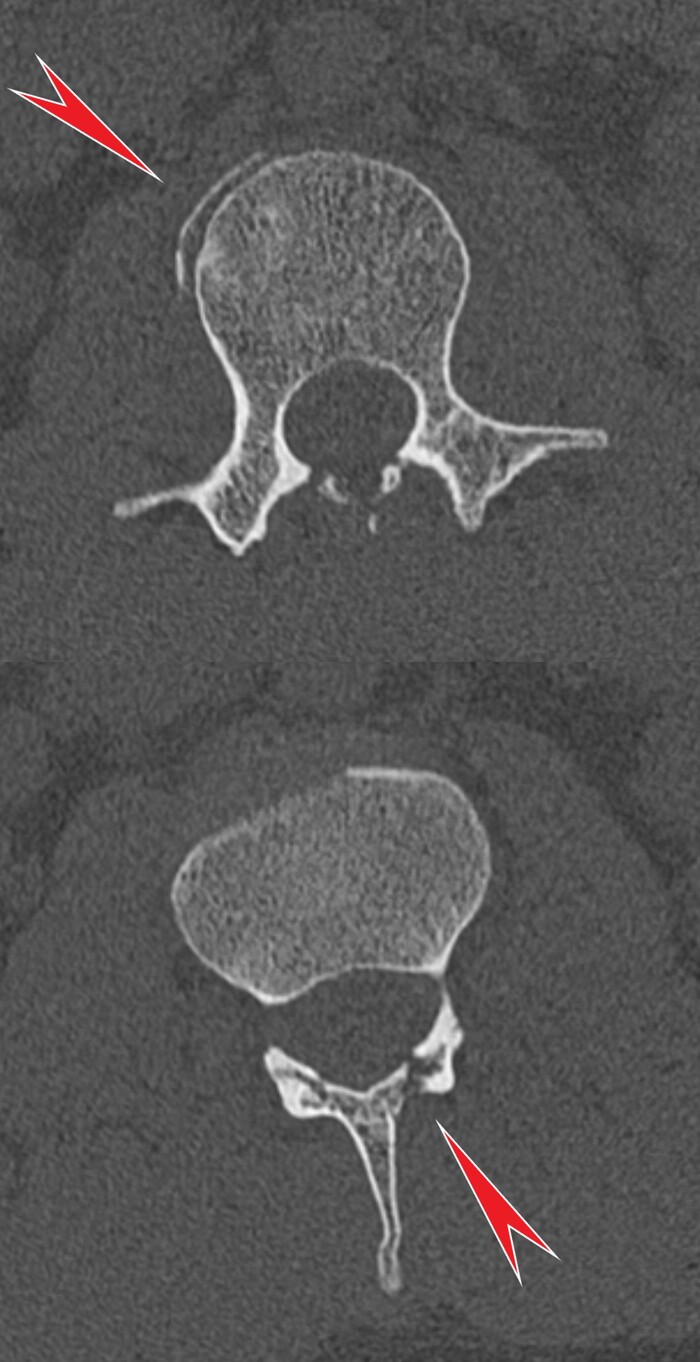

Ну и в довесок на SWI-изображениях (специальная импульсная последовательность, взвешенная по магнитной восприимчивости, усиливает сигнал от продуктов распада гемоглобина, что значительно повышает способность распознавать мельчайшие кровоизлияния в головном мозге) были выявлены очаги микрокровоизлияний в поражённых участках + в верхней ножке мозжечка и вдоль кортико-спинального тракта справа (чёрные пятна на изображениях):

В нашем случае это было ДАП 3 (максимальной) степени тяжести.

Девочку перевели в соседнюю крупную клинику для дальнейшего наблюдения / лечения. 2 недели спустя наш нейропедиатр сообщил, что она так и не пришла в сознание, продолжая оставаться в состоянии комы. Дальнейшая её судьба мне не известна.